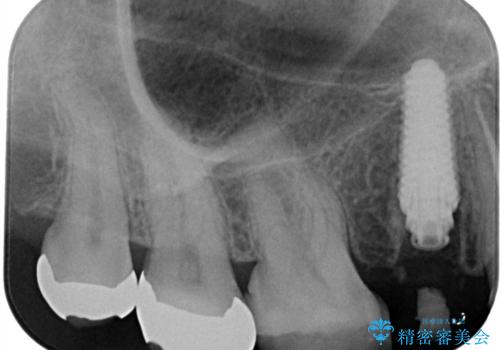

1日で抜歯、インプラント埋入、骨補填材を填入し仮歯【1DAYインプラント】までを数時間で行いました。

術後もほとんど痛みがなく経過も良好です。

3ヶ月後には、オールセラミック治療も終わり、短期間治療の為とても楽でしたと喜んでいただけました。